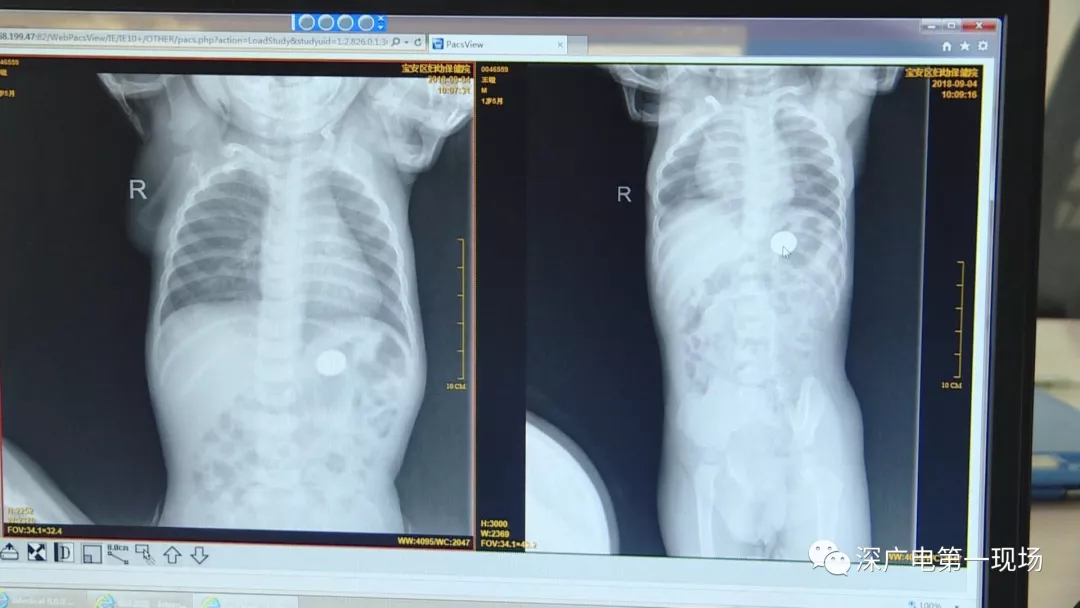

在術(shù)前檢查中

細(xì)心的醫(yī)生竟從

孩子的胸片中有了意外發(fā)現(xiàn)

9月4號(hào),一名1歲零5個(gè)月的男嬰因在家中摔傷,被父母送到了寶安區(qū)婦幼保健院,醫(yī)生診斷為左側(cè)尺橈骨骨折。在進(jìn)行全麻手術(shù)之前,院方例行對(duì)嬰兒進(jìn)行了周身檢查。手術(shù)前,兒外科醫(yī)生趙冠聰在查看患者的胸片時(shí),發(fā)現(xiàn)這名嬰兒的胃部有一枚硬幣大小的暗影。

在與多名醫(yī)生會(huì)診之后,醫(yī)生擬定了聯(lián)合手術(shù)方案。

胃部取出一角硬幣

已吞咽半月之久

經(jīng)過兩個(gè)小時(shí)的時(shí)間,兒科醫(yī)生郭景濤為患兒取出了藏在胃底的一角錢硬幣。目前,患兒已經(jīng)痊愈出院。